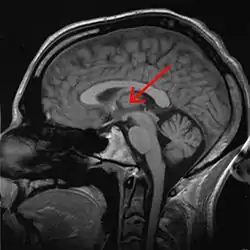

تالاموس

تالاموس (thalamus) یا نهنج یکی از سازوارههای دستگاه کنارهای (لیمبیک) در مغز و محل تقویت و پردازش اطلاعات است.[1]

الیاف اعصاب حس پنجگانه بدن انسان به جز حس بویایی برای تقویت وارد تالاموس شده و سپس از تالاموس خارج و وارد قشر مخ برای پردازش میشود. تقویت نشدن حس بویایی انسان توسط تالاموس از دلایل اصلی ضعیف بودن این حس در انسان نسبت به دیگر حیوانات مانند سگ میباشد. همچنین تالاموس مسئول تطبیق تصویرها با عواطف میباشد. تحریک هستههای میانی، پسین و پیشین تالاموس به دگرگونی در پاسخهای احساسی میانجامد؛ ولی اهمیت این هستهها در تنظیم رفتارهای احساسی به واسطه خود تالاموس نیست بلکه به چرایی ارتباط این هستهها با دیگر سازههای دستگاه کنارهای میباشد.

اجزای تالاموس :هسته ی شکمی قدامی(ventral anterior) ٬ هسته ی شکمی جانبی(ventro-lateral nucleus) ٬ هسته ی شکمی خلفی جانبی(ventro-postero-lateral) ٬ هسته ی شکمی خلفی میانی(ventro-postero-median) که در داخل هسته ی شکمی خلفی جانبی قرار دارد و هسته ی پولوینار(Pulvinar) که خلفی ترین هسته ی تالاموس است.